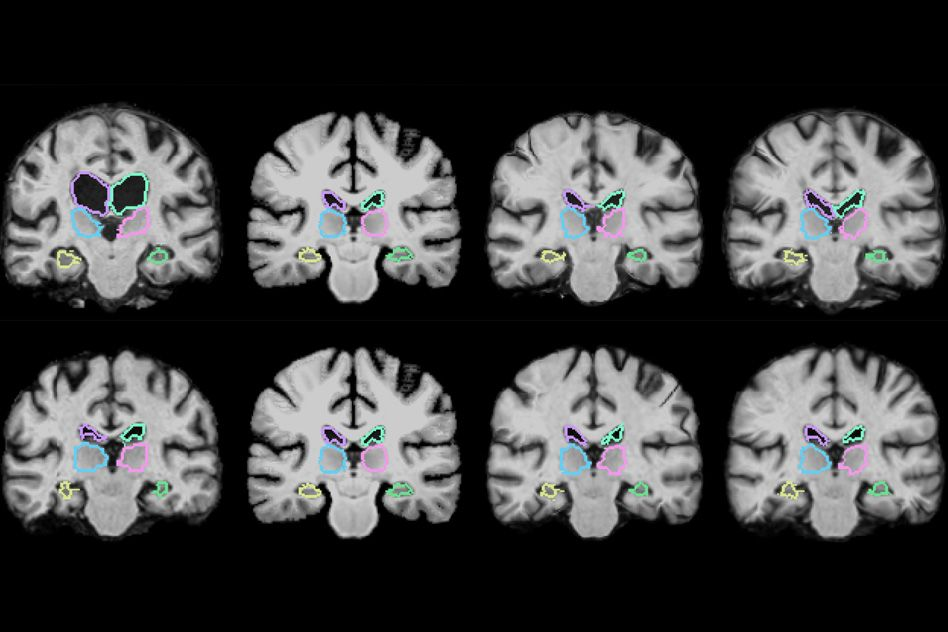

- Convolutional Neural Networks (CNNs): These are particularly effective for image analysis. CNNs are widely used in medical imaging devices to detect and classify abnormalities in X-rays, CT scans, and MRIs. For instance, CNNs have been successfully applied to analyze retinal images for diabetic retinopathy screening (PMC, Dec 12, 2023) and to achieve high accuracy in diagnosing illnesses from thermogram data (Nature, June 4, 2025).

Coronal brain MRI scans showing neural network-based segmentation of brain structures